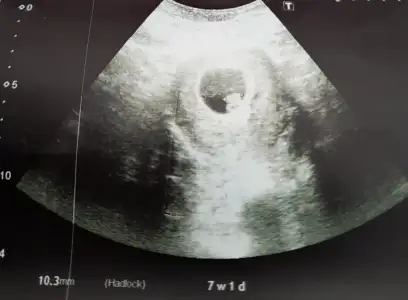

Kalp atışlarını duyduk bugün çok şükür 6+4 te🤲 7 mm boyundaymış 😊kese solda hayırlısı olsun insAllah hepimiz için

Benim minnoşum da burada 🥰

Normal gözüküyor dmi mm🙏🎈